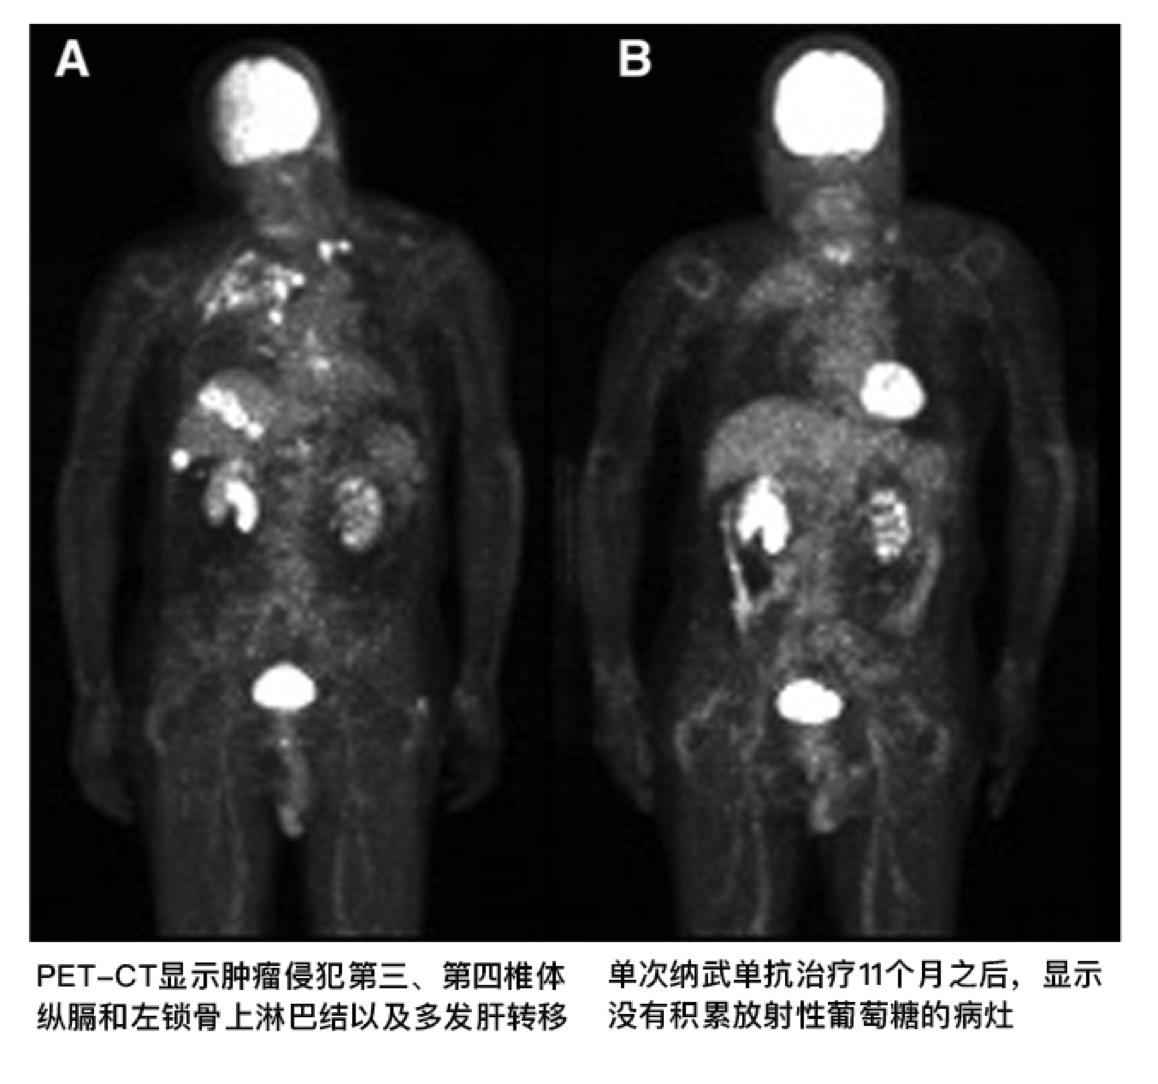

病人紧急入院两个月之后,开始了培美曲塞的单药治疗,随后病人的全身状况得以逐渐好转,然而经过12个疗程的培美曲塞治疗,PET-CT影像学检查显示出现了多发性肝转移,左锁骨上淋巴结转移。得知病情进展之后,病人的精神因焦虑而一度崩溃。

再次CT检查发现肝部转移灶逐渐萎缩,最后病灶完全消失,肿瘤原发灶也逐渐地缩小,之前被肿瘤破坏的椎体逐渐被纤维和钙化组织替代,PET-CT再次检查没有发现异常的肿瘤病灶。病人双侧下肢的麻痹消失了,也逐渐地停用了羟考酮和氧疗。